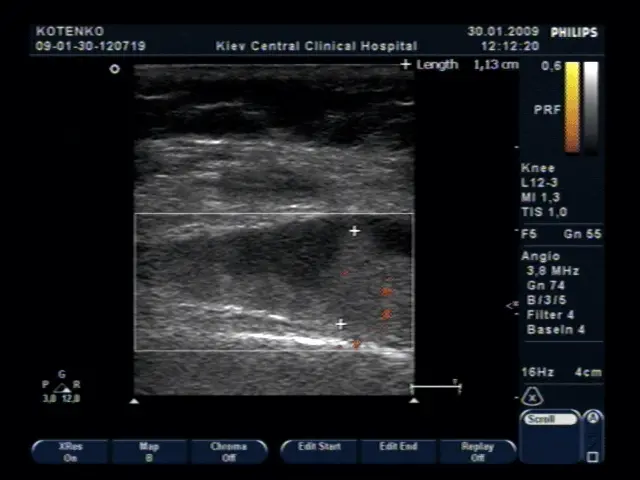

УЗД коліна — достатньо точний метод діагностики патології м’ягких тканин суглоба. УЗД дозволяє бачити запалення, уточнювати стан синовіальнї оболонки, об’єм рідини в коліні, її локалізацію і ті.

Проліферація синовіальної оболонки коліна при кісті Бейкера (фото нижче)

Оцінка стану суглобового хряща коліна, що вкрай важливо при артрозі (фото нижче).

Оцінка кровотоку в синовіальній оболонці колінного суглоба